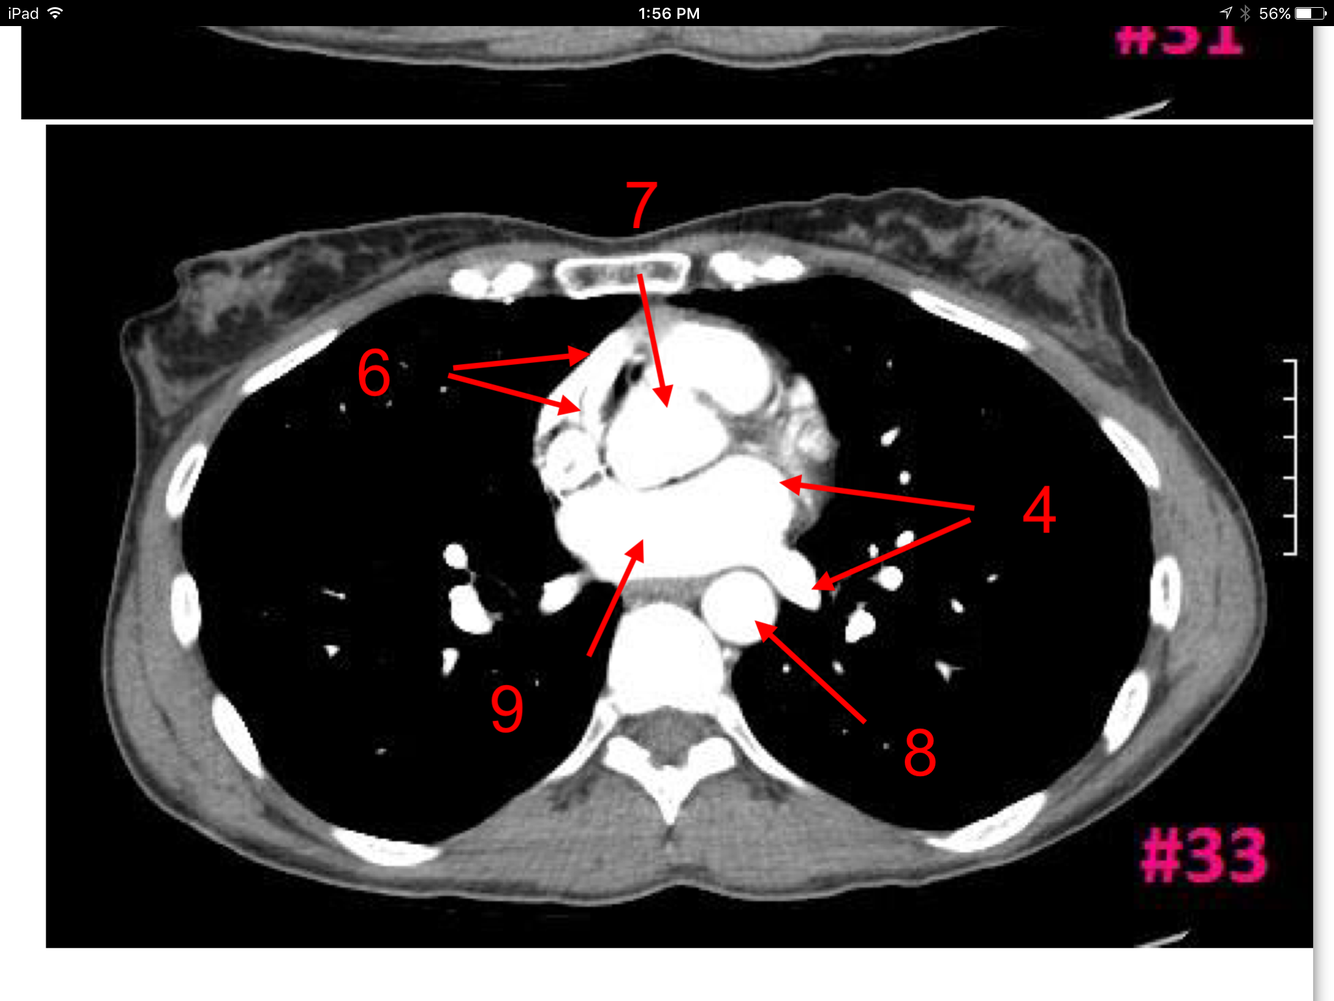

15

Q

A

Superior vena cava

Ascending aorta

Descending aorta

Lt pulmonary artery

Lt main bronchus

Rt main bronchus

Rt pulmonary artery

Rt intervertebral foramen

How well did you know this?